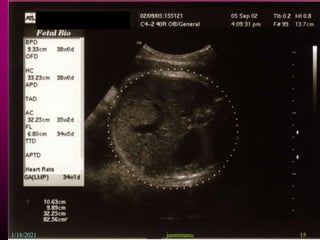

This document provides information about intrauterine growth restriction (IUGR), including its definition, classification, etiology, diagnosis, treatment and risks. IUGR occurs when a baby's growth is slowed or restricted during pregnancy. It can be symmetric, affecting overall growth, or asymmetric, affecting the growth of some parts more than others. The causes of IUGR are often unknown but can include maternal, fetal, placental or genetic factors. Diagnosis involves assessing growth via ultrasound and monitoring blood flow. Treatment may involve bed rest, aspirin or early delivery depending on gestational age and fetal wellbeing. Both short and long term risks to the infant are increased with IUGR.